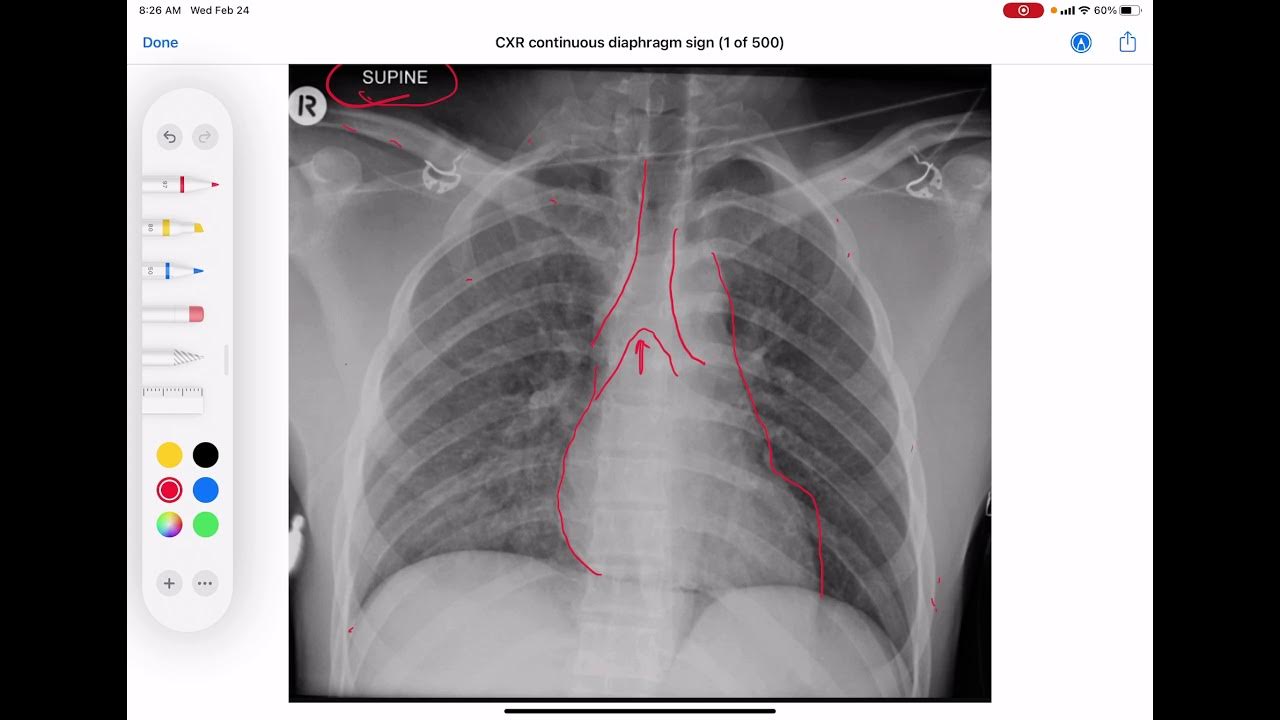

From www.youtube.com

CXR Continuous diaphragm sign YouTube How To Check Diaphragmatic Excursion Percuss from the lower edge of his right scapula down toward the diaphragm (see technique for percussion ). Diaphragm excursion and tfdi are useful to detect diaphragm weakness. To measure diaphragmatic excursion, ask your patient to inhale and hold it. The fluoroscopic sniff test is a useful addition to diaphragm fluoroscopy and is used to evaluate diaphragmatic contraction and excursion. How To Check Diaphragmatic Excursion.